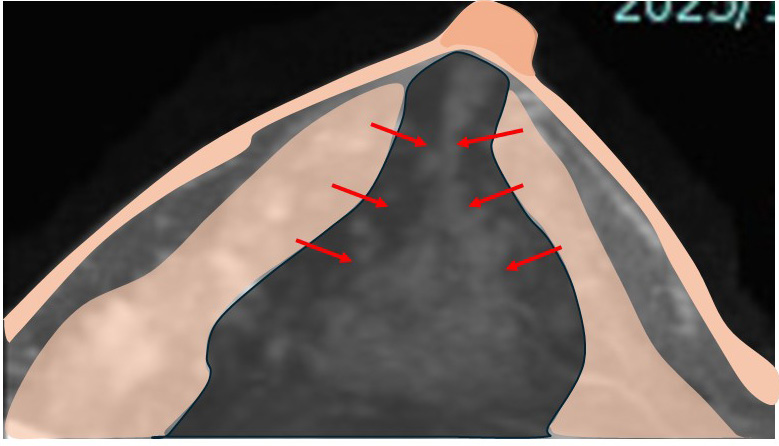

何故ここまで引っ張れるかって?

↓

それは乳腺が立体的(厚みを持っている)からです。

乳腺に厚みがあるから引き延ばせて縫合できるのです!

この症例の実際の傷(術後1日目)

センチネルリンパ節生検の傷(上)

乳腺切除の弧状切開(下)

変形は殆どなし

手術自体は…

乳腺の切除範囲も(温存としては)比較的広いけど、皮膚は切除しているわけではないので、表面上は「小さな創」があるだけとなります。

つまり乳腺を「広範囲に切除し、長い距離縫合」しても(それは表面=皮膚面からは)見えないので、「結構な広範囲で切除した感」は、まるで無いのです。